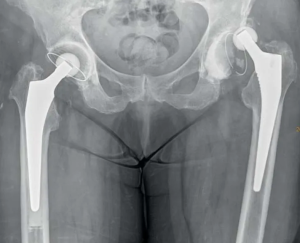

Хирургическое лечение вывихов головки эндопротеза тазобедренного сустава

В ФГБУ «НМХЦ им. Н.И. Пирогова» в период с 2013-2022 гг. 15 168 пациентам проведено первичное эндопротезирование тазобедренного сустава, и зафиксировано 117 вывихов головки эндопротеза (0,77%).

В исследование первоначально включены 67 пациента с коксартрозом, которым провели тотальное эндопротезирование тазобедренного сустава, с возникшим в послеоперационном периоде вывихом головки эндопротеза. Моноцентровой анализ проводили ретроспективно по историям болезни пациентов, лечившихся в 2015- 2022 гг. Трое пациентов исключены: двое в связи с выявленной нестабильностью компонентов эндопротеза, один - в связи с невозможностью получить сведения о послеоперационном периоде амбулаторного лечения.

В ходе анализа сформированы две группы: в первую вошли 26 пациентов лечившимся по исследуемой методике, во 2-ю группу - 38 пациентов получившим оперативное лечение другими хирургическими методиками. Критерии включения в исследование: -коксартроз, по поводу которого проведено тотальное эндопротезирование тазобедренного сустава; - тотальное эндопротезирование тазобедренного сустава из переднебокового доступа; - соответствие физического статуса пациента классу ASAII по классификации Американской ассоциации анестезиологов; возникновение вывиха головки бедренного компонента эндопротеза в срок до 3 лет после операции; катамнез, прослеженный в сроки не менее 2 лет после ревизионного эндопротезирования тазобедренного сустава. Критерии исключения: -невозможность получения данных о пациенте после ревизионного эндопротезирования в течении 2 лет.

Для лечения пациентов первой группы применена методика при которой проводили установку и фиксацию антилюксационного кольца («козырька») винтами к имеющейся чашке (Рис. 1) или полиэтиленовому вкладышу эндопротеза (Рис. 2), что приводит к замыканию сферической головки эндопротеза в тазовом компоненте, что делает невозможным их разобщение, обеспечивая тем самым профилактику вывиха головки эндопротеза в течение длительного времени.